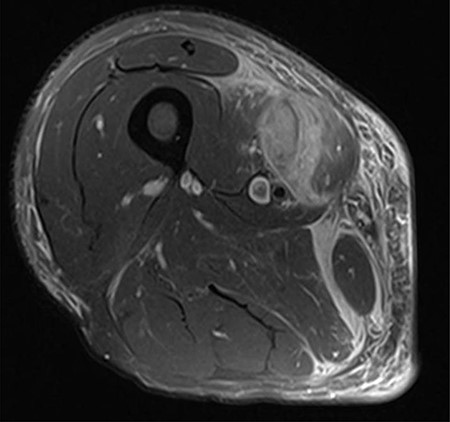

The clinical case consisted of a 79-year-old male patient with a medical history of atrial fibrillation and pulmonary embolism diagnosed 2 years ago. Among the prescribed medications, rivaroxaban was given as an anticoagulant therapy. The patient was lying in bed when a sudden onset of a sprain-like pain appeared on his right thigh region. He had difficulty walking and observed the progression of a large ecchymosis along the thigh, extending from the greater trochanter of the femur to above the patella. Later as the clinical manifestations worsened, the patient arrived at the emergency department. At the hospital, the treating physician noticed edema, ecchymosis and pain confined to the thigh region; therefore, ordered laboratory studies, such as prothrombin time, international normalized ratio and hemoglobin were all within the normal range for the patient’s age and comorbidities. The doctor solicited a magnetic resonance imaging (MRI) study to evaluate the thigh region where a rupture and hematoma regarding the sartorius muscle was evident. The MRI displayed a hyperintense area representing blood collection and discontinuity in the trajectory of the sartorius muscle (Figs 1–3). The hematoma was large in volume, hence surgical drainage was performed. After the procedure, the patient’s pain diminished considerably and was ordered to rest. Posteriorly, the patient began rehabilitation exercises and cooperated with follow-up dates to test progression. The patient attended a follow-up appointment after 6 months of initial presentation where a positive clinical outcome and enhanced walking capacity was observed.

MRI coronal view displaying hematoma and rupture of sartorius muscle.